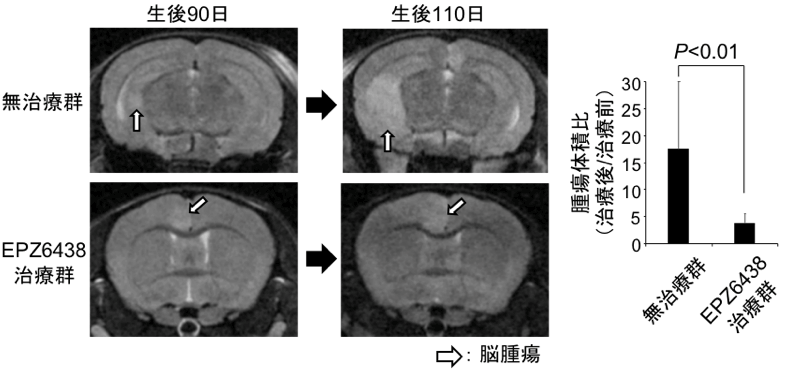

腫瘍が形成されていく過程で、EZH2は多くの重要な遺伝子に異常なヒストン修飾(H3K27me3修飾)を引き起こし、それらの遺伝子発現を異常調節していることがわかりました。次いで、遺伝子操作によりMADMマウスのEzh2遺伝子をノックアウトすると、これらの異常なヒストン修飾を受けた遺伝子の発現は正常化し、腫瘍の増大は抑えられました。EZH2は有望な治療標的であると考え、MADMマウスにEZH2阻害剤(EPZ6438)を投与しMRIで腫瘍体積を評価したところ、EPZ6438の投与により腫瘍の増大が抑えられることがわかりました(図2)。また、ヒトでもIDH遺伝子変異がない低悪性度神経膠腫ではEZH2が高発現しており、本腫瘍の中で特にp53,NF1遺伝子異常がある細胞株(TM31)にEPZ6438を投与すると同様に細胞の増殖が抑えられることが明らかになりました。

図2.EPZ6438による腫瘍の増大抑制効果